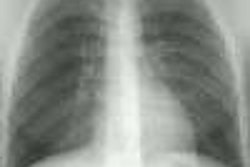

Anatomists divide the mediastinum into four parts- the superior and inferior mediastinum (separated by an imaginary line traversing the manubrial joint and the lower surface of T4), and then the inferior compartment is divided into the anterior, middle (containing the heart, major blood vessels and airways), and posterior mediastinum [2]. Felson divided the mediastinum based upon the lateral CXR with the anterior mediastinum bounded anteriorly by the sternum and posteriorly by a line drawn from the anterior aspect of the trachea and along the posterior heart border; the posterior mediastinum is defined by a line that is 1 cm posterior to the anterior edge of the vertebral bodies; and the middle mediastinal compartment lies between the anterior and posterior mediastinum [2].